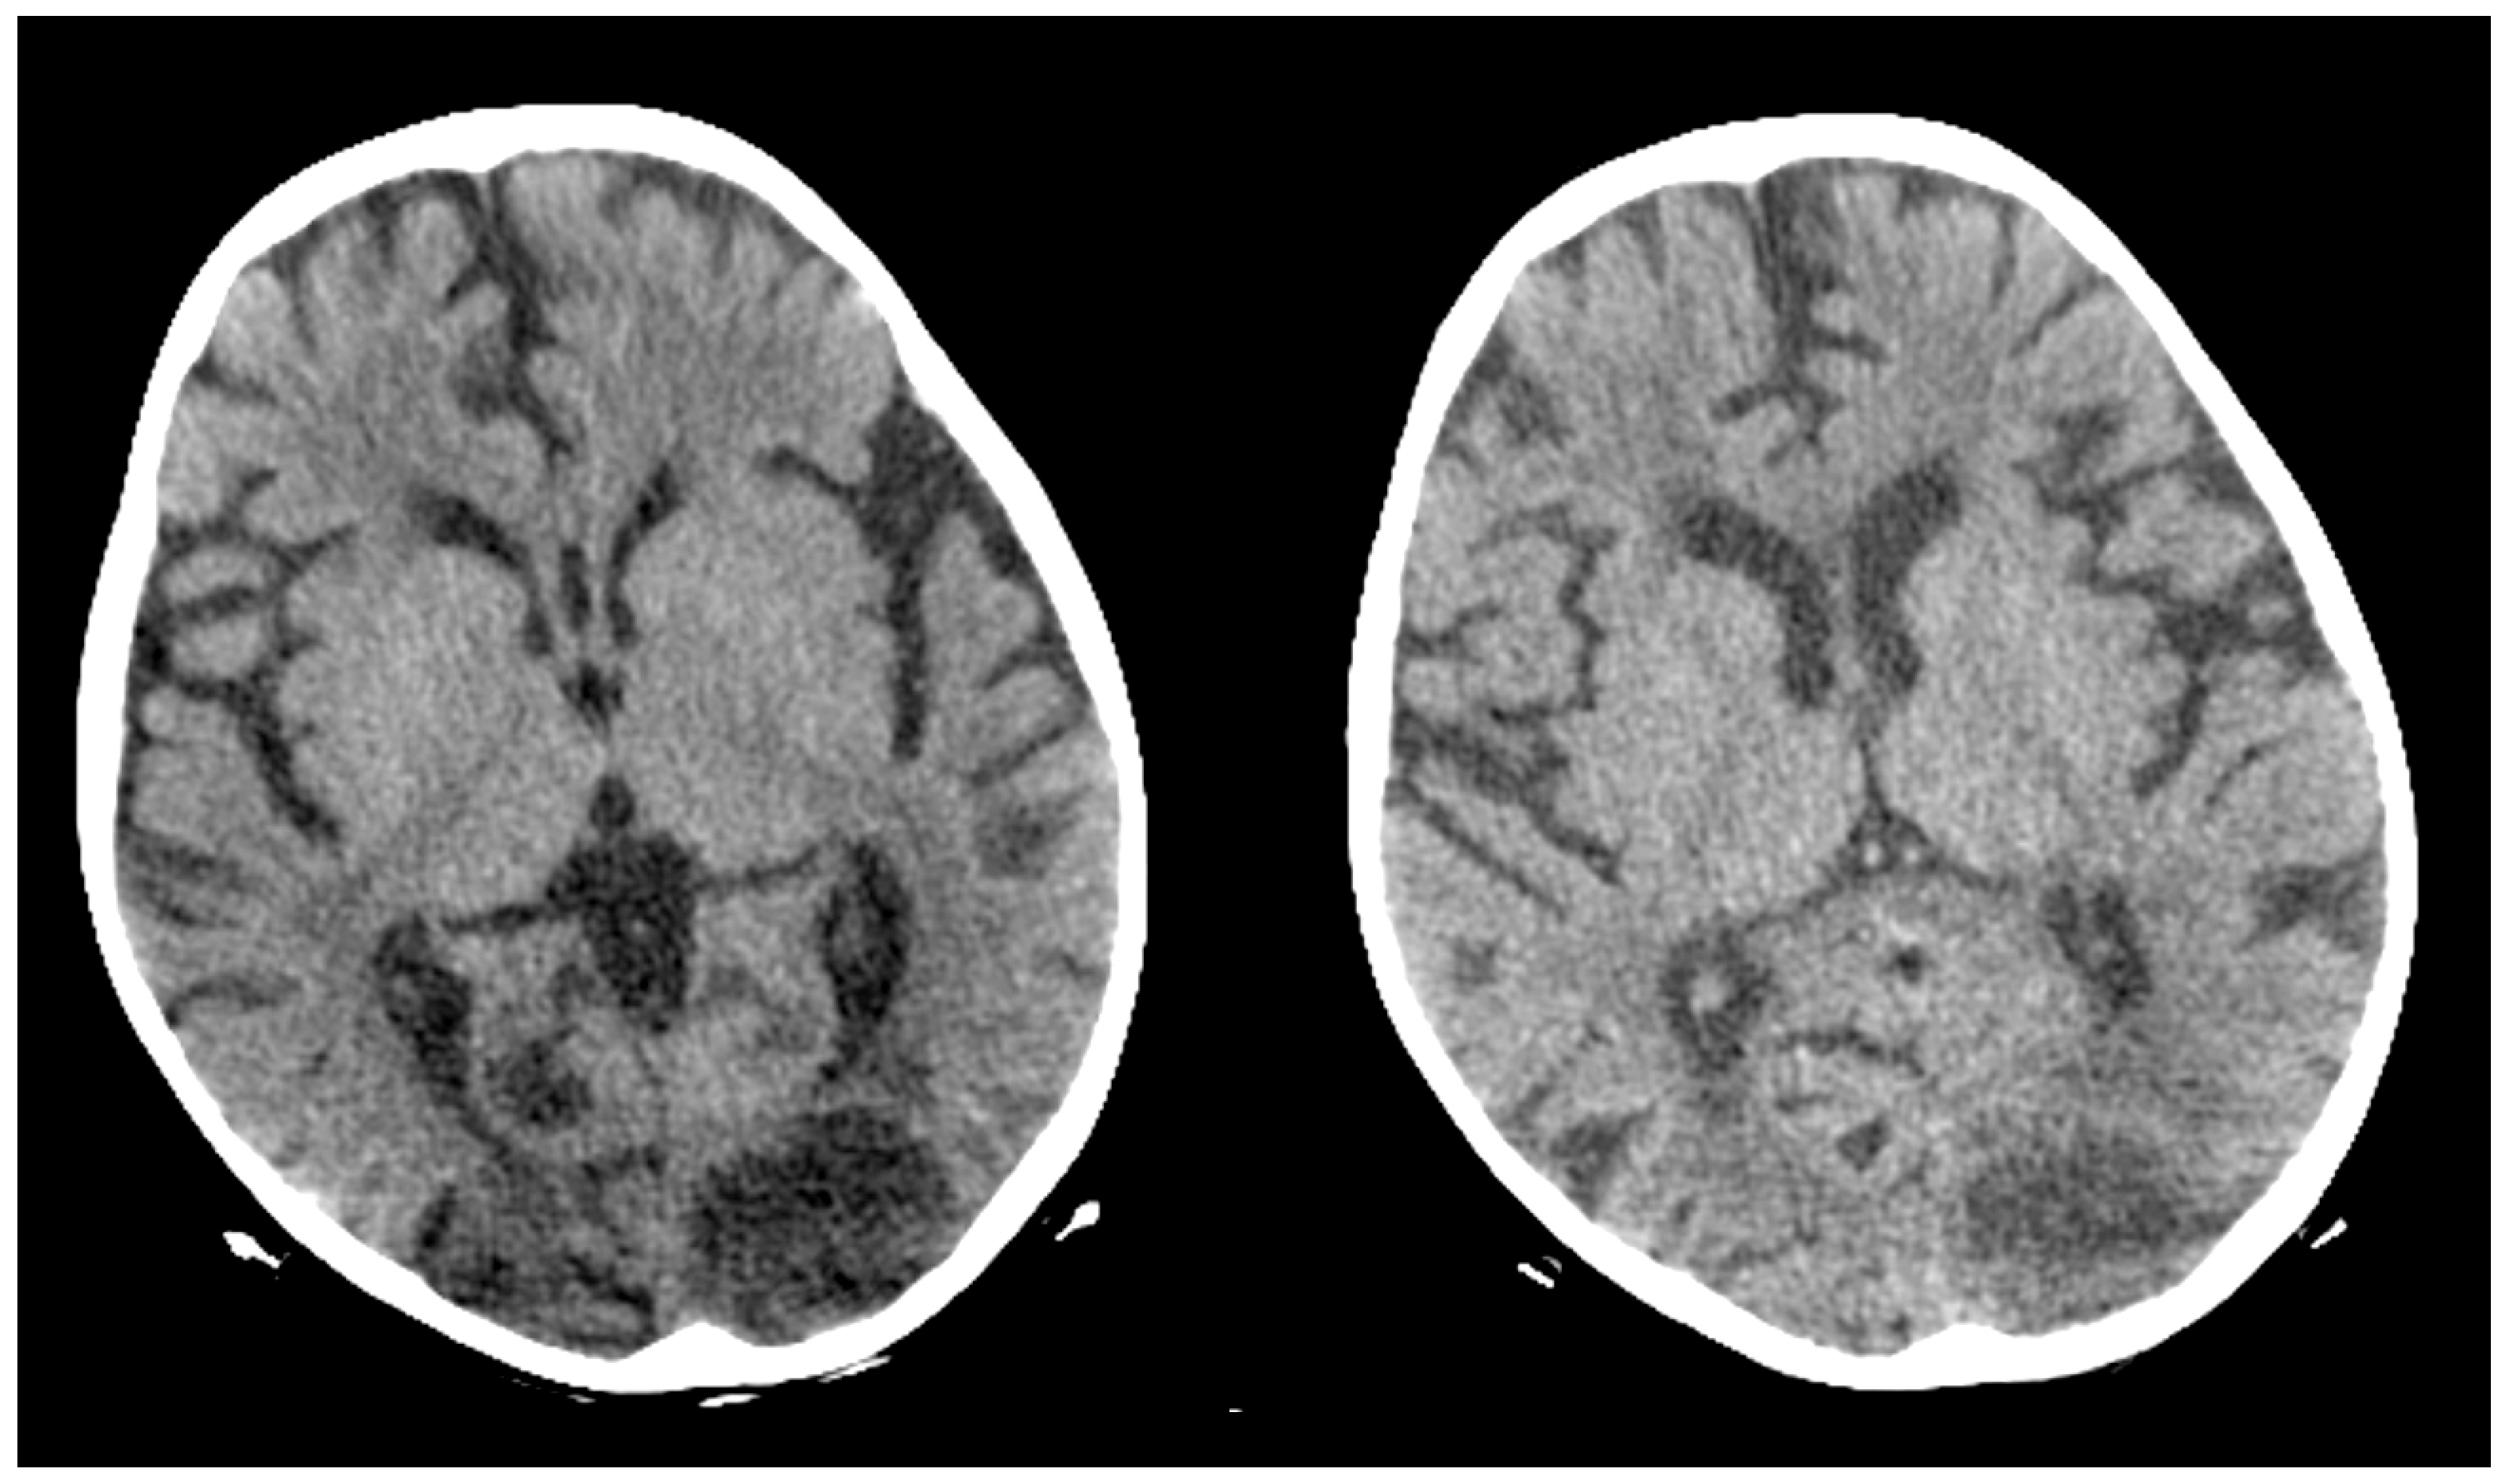

2. Case Report